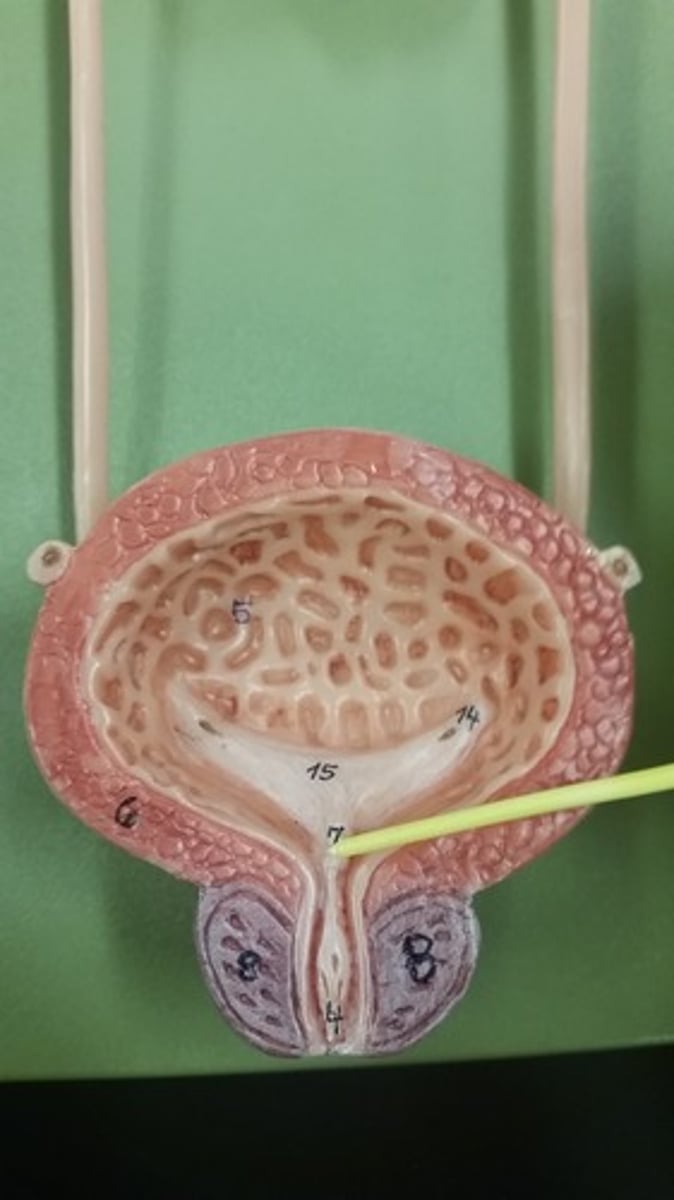

urinary bladder

urinary bladder

detrusor muscle

layer

internal urethral sphincter

bladder neck

external urethral sphincter

ureteric orifice

trigone of bladder

rugae

Urethra